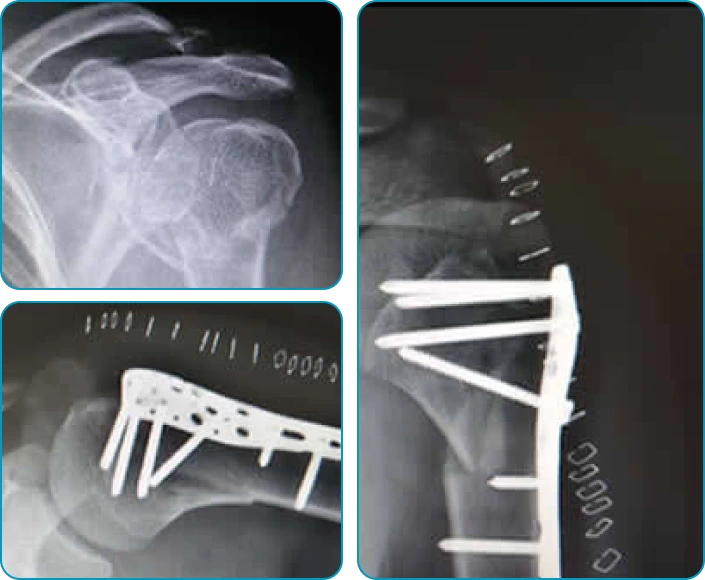

• Fracturas del húmero.

Cirugía de Columna GuadalajaraFractura (hueso roto)

• Fracturas del húmero: Si una fractura del húmero es grave y el hueso no puede sanar por sí solo, puede ser necesario realizar una cirugía para fijar el hueso con placas, tornillos u otros dispositivos.